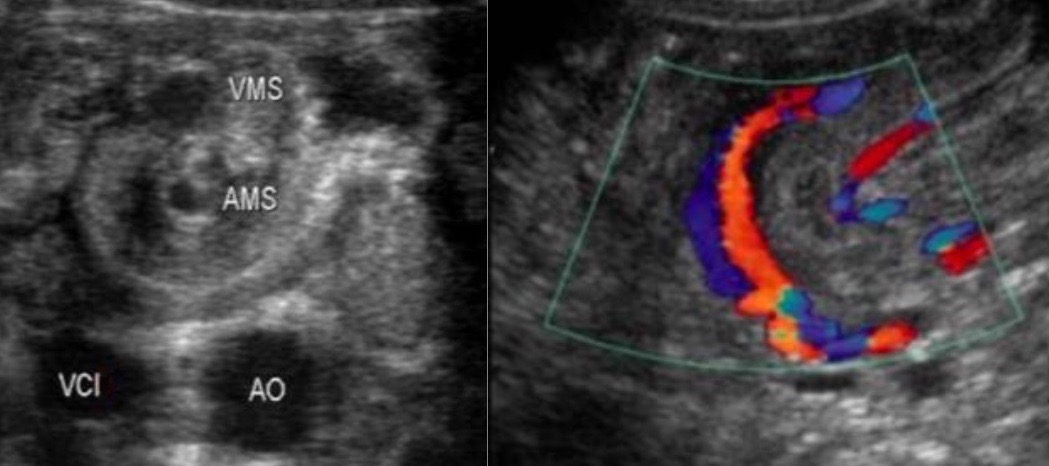

- vomis bilieux NNé < S2 à ventre plat, 80% < 1 an mais peut survenir à tout âge

- complique une mésentère commun incomplet (malrotation intestinale)

signe du tourbillon => PEC chirurgicale immédiate

signe du tourbillon => PEC chirurgicale immédiate

écho non contributive / négative => opacification digestive haute

écho non contributive / négative => opacification digestive haute